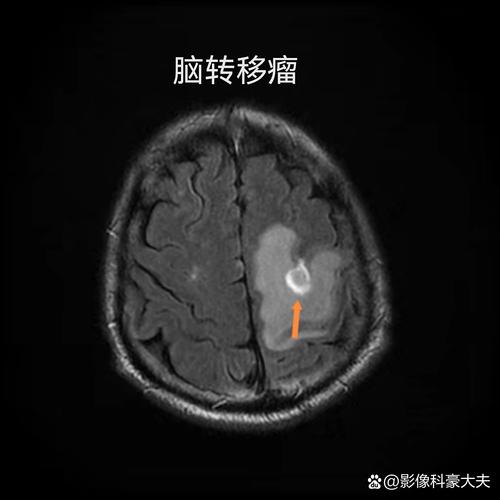

脑磁共振诊断脑梗的“王牌武器”:弥散加权成像(DWI)

这是诊断急性期(尤其是超早期)脑梗死的金标准。

- 工作原理:在细胞刚缺血坏死的最初几分钟到几小时内,细胞膜的离子泵功能衰竭,导致水分子从细胞外大量涌入细胞内,这种水分子运动受限(弥散受限)的现象,只有DWI序列能够非常敏感地捕捉到。

- 表现:在DWI图像上,缺血的脑区域会呈现出明显的高信号(亮白色),而周围的正常脑组织呈低信号(黑色),这种对比度极高,使得即使非常小的梗死灶也能被清晰显示。

- 时间窗:DWI在发病后30分钟到1小时就可能发现异常,而传统的CT检查通常要在发病后6小时甚至更长时间才能看到模糊的低密度灶,对于急性脑梗死患者,时间就是大脑,DWI的早期发现对于及时治疗(如溶栓、取栓)至关重要。